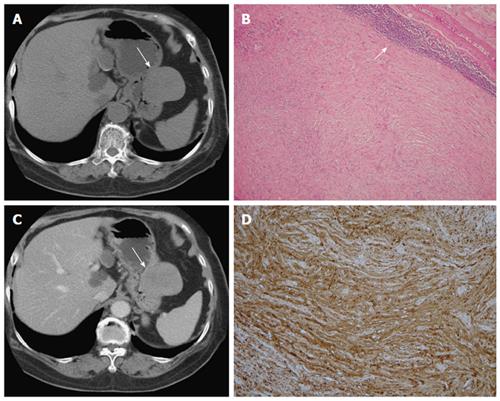

Epidemiology gastric diverticula are rare and c. Weight loss surgery is about reducing your weight and gaining good health. Gastric diverticula are sac like projections that usually originate from the gastric fundus most commonly on the posterior surface. They are the least common of the gastrointestinal diverticula.

Cain jc jordan gl jr comfort mw gray hk. J am med assoc. The gas tric fundus is dened as the portion of the stomach craniad to the gastric car dia. Commonly accompanying this are abnormally dilated short gastric veins which pass from the splenic vein to encircle the gastric fundus and form gastric fundal varices.